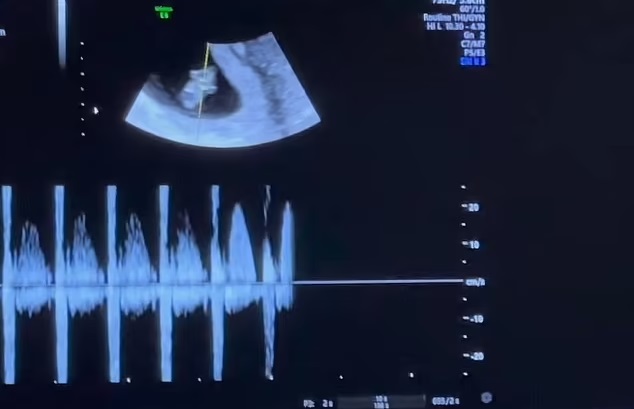

The 39-year-old American model and TV reality star broke the happy news on Instagram as he shared a video showing his partner, a 25-year-old professional surfer, getting an ultrasound.

Brody also shared a heartwarming video showing Tia smiling from ear to ear while getting an ultrasound done by her doctor.